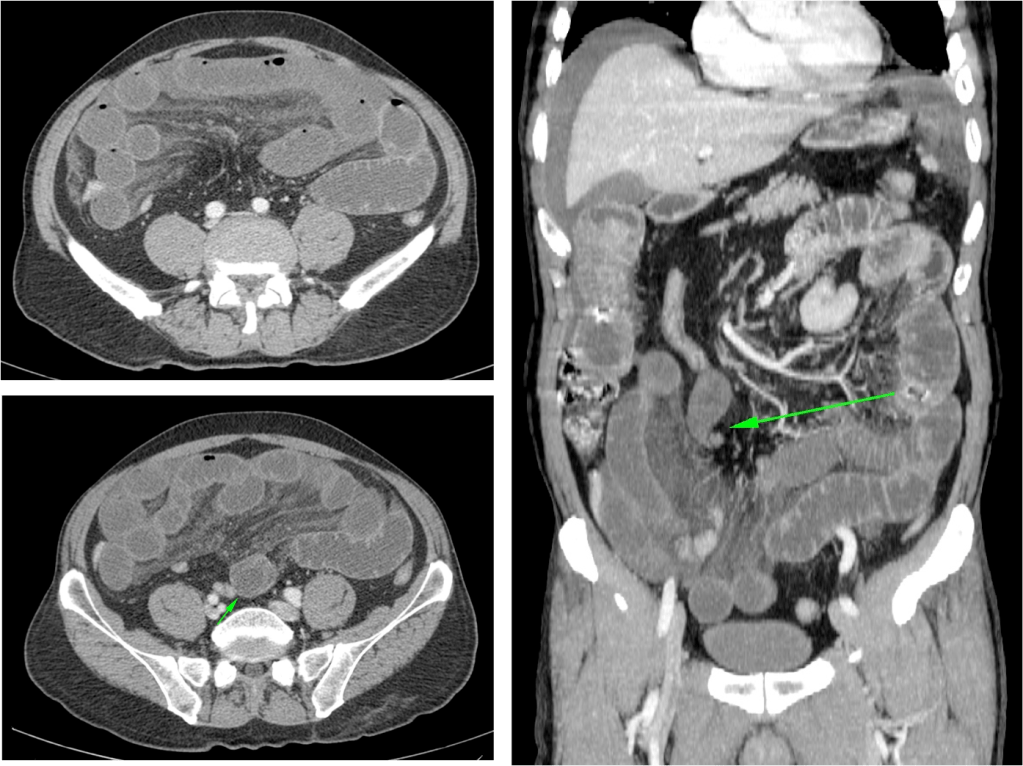

OTRAS CAUSAS:

Cuerpo extraño: Más frecuente en niños o pacientes psiquiátricos, suele localizarse en intestino delgado.

Lipoma intestinal: frecuente como punto guía o cabeza de invaginación en el instestino delgado. Aquí presentamos un caso de lipoma intraluminal en el colon, que producia obstrucción y cambios inflamatorios en el colon ascendente.